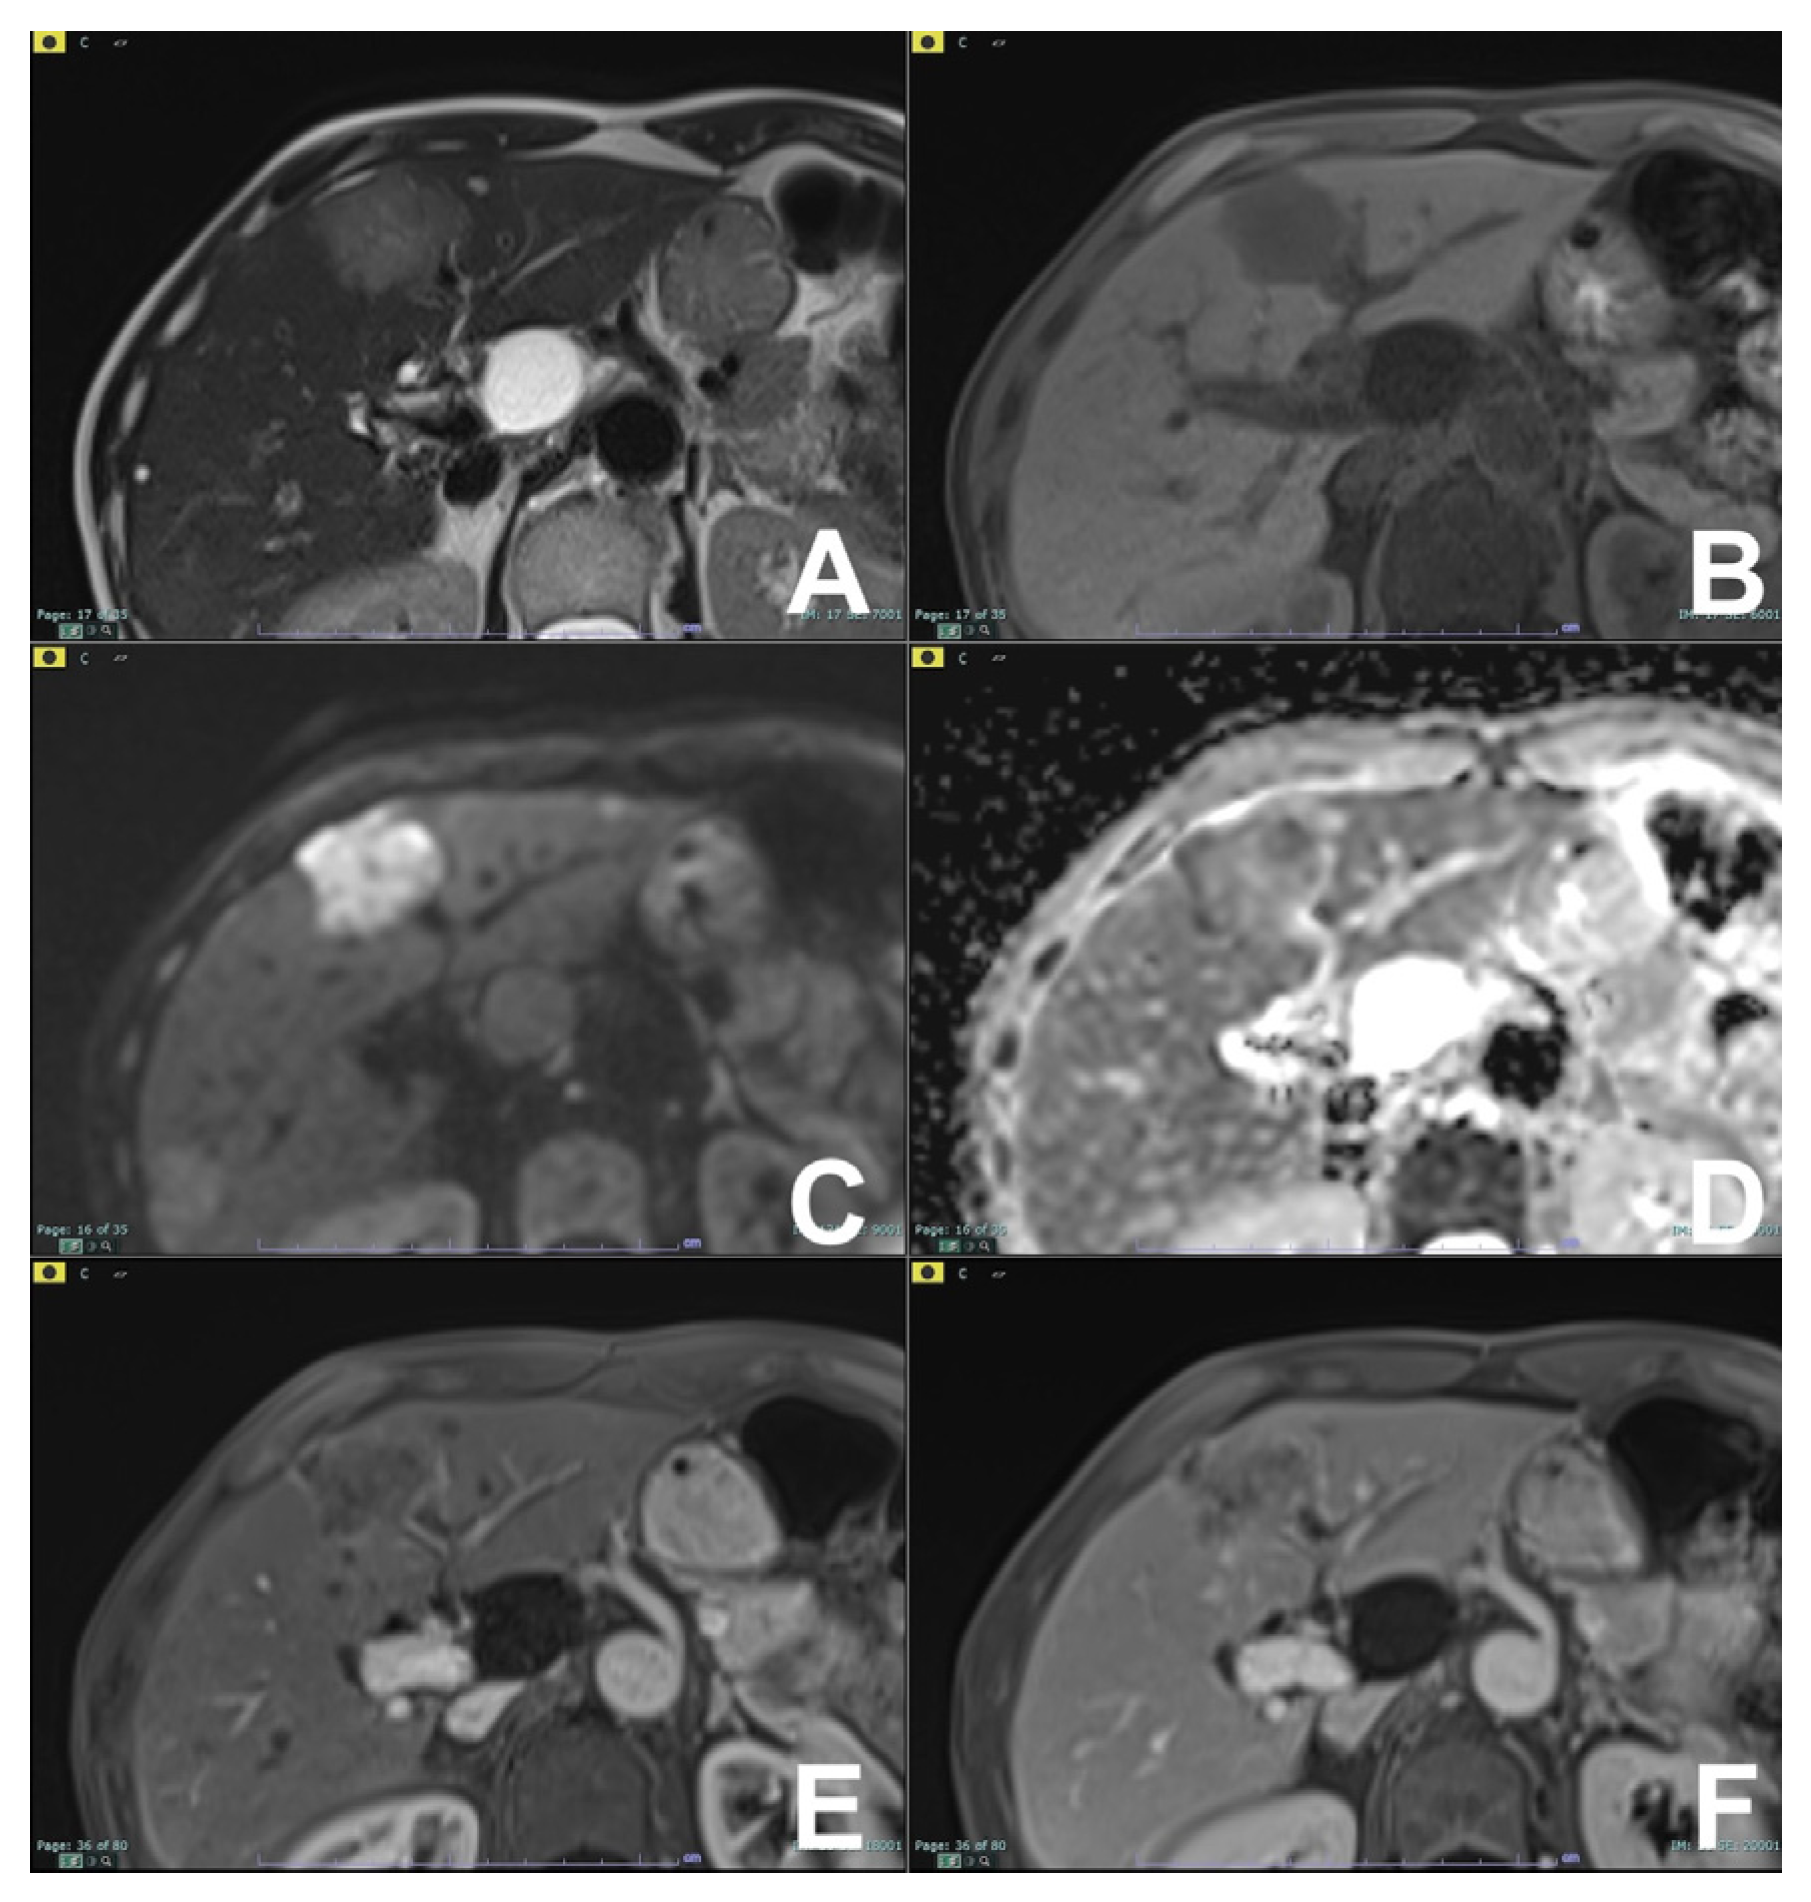

| GRE T1 3D DYNAMIC | AXIAL | PRE-ART 25″-PORTAL 70″-LATE 180″ | YES (if the lesion is hypervascular) | Benign hypervascular hepatocitic lesions appear hyperintense in HBP | |

| Cirrhotic liver: characterization of FLL/Follow-up after treatment | HASTE T2 | AXIAL | -- | -- | Anatomy and liquids analysis |

| INDICATIONS: MRI is the technique of choice in young patients and pregnant women after a unclear US finding. Moreover, it is useful even after a CT with undefined diagnosis for all patients. | HASTE T2 | CORONAL | -- | -- | Anatomy and liquids analysis |

| DWI b 0–50–400–800 | AXIAL | -- | -- | High signal in b 800 suspicious for HCC | |

| GRE T1 IN/OUT | AXIAL | -- | -- | Steatosis | |

| GRE T1 3D DYNAMIC | AXIAL | PRE-ART 25″-PORTAL 70″-LATE 180″ | YES (if the lesion shows atypical enhancement) | Hypointensity in HBP suspicious for HCC | |